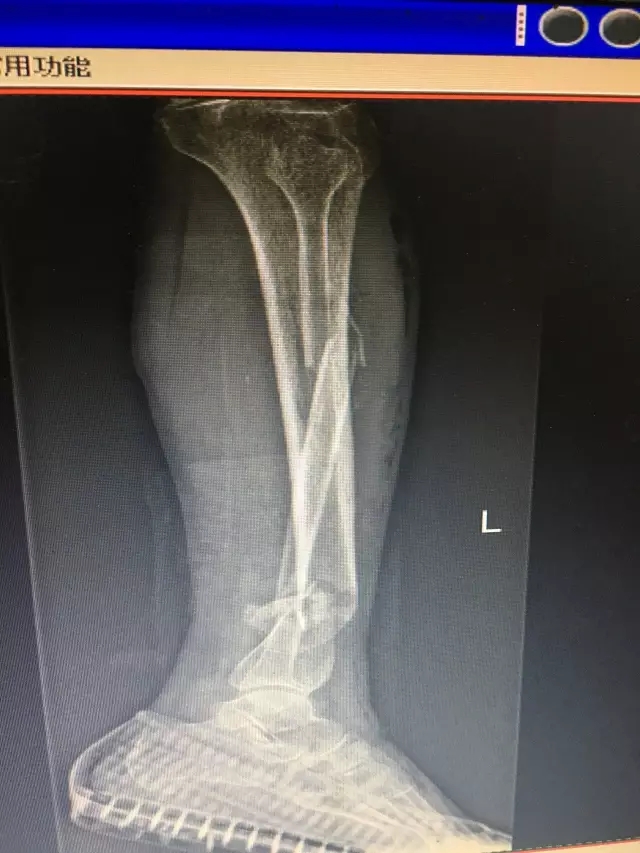

7月26日,99岁高龄的付奶奶不慎被小汽车撞伤,当时感到左下肢疼痛难忍,并有出血,无法站立。随即120将老人送至捕鱼游戏 急诊科,拍片后被诊断为“开放性左胫腓骨粉碎性骨折”,随即转入医院骨科住院治疗。

由于患者是一名年近百岁的老人,骨科主任闵志海反复地对患者身体状况进行了评估,并组织科室医生进行阅片,讨论手术方案。认为如果保守治疗,老人少说也要卧床三个月,而高龄老人最怕卧床不起。大家最后决定尽快为老人手术治疗,术前还邀请了麻醉科医生进行会诊,根据老人的身体状况选择了对患者影响最小的神经阻滞麻醉。